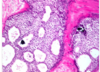

Q

A

TL: invasive ductal

TR: insitu ductal

BL: invasive lobu

BR: insitu lobular